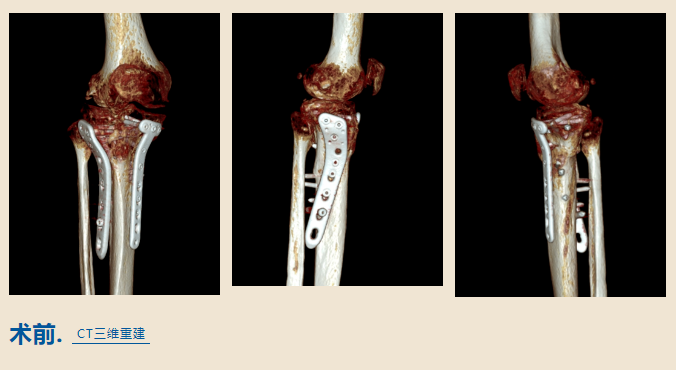

造成了右腿的胫骨平台骨折

在当地医院手术治疗后

结果却不尽人意

骨折部位畸形愈合

因为有很多骨缺损、技术难度

比如膝关节局部软组织

瘢痕松解困难

术中关节面显露困难